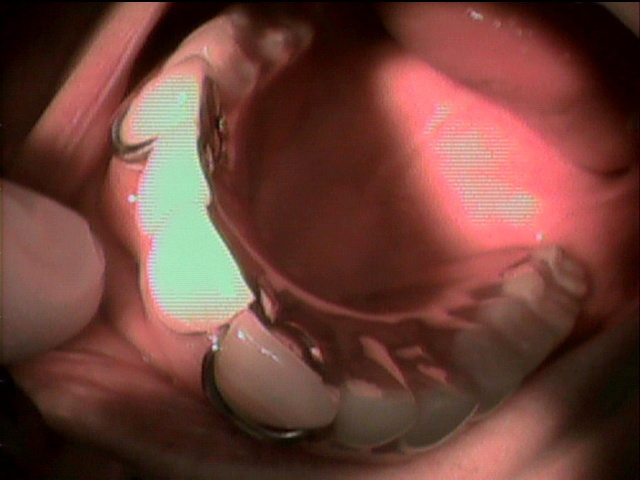

上の入れ歯がこわれてしまって、来院されました。のこっている上の前歯の6本分がつながったブリッジは歯ぐきが根元ではれていてぐらぐら状態。全く噛む場所がありません。

診断すると、残っている前歯4本は歯の中がほとんどくさってしまっていました。

残念ながら前歯はすべて抜かなくてはならず、上の歯は総入れ歯としてまず治療用入れ歯を事前に準備することから開始しました。同時に歯ぐきの腫れの消炎処置をしました。

前歯のつながった歯を切り離し、同時に歯を抜き、その日にすぐに仮の入れ歯を装着することとしました。

顎の粘膜の調整をしながら経過し、上の入れ歯との噛み合わせを調整していきます。

顎の状態が良好になってきました

約2ヶ月後最終入れ歯を入れた状態です。

初診から最終調整まで、前歯がなくなってしまう見栄えが悪い事は一日もなく治療を進行することができました。

現在 右も左もしっかりと噛む事が出来ます。